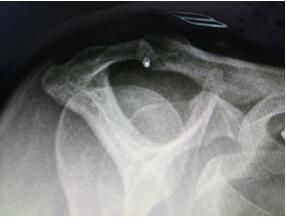

???????????????????X片檢查發(fā)現(xiàn)患者為三型肩峰

“患了肩峰撞擊綜合征,通常只要適量運(yùn)動(dòng),經(jīng)過充分休息是不會(huì)發(fā)生肩痛的。但是有一類人群應(yīng)當(dāng)注意,那就是三型肩峰。”李彬主任進(jìn)一步說到,肩峰撞擊綜合征分為三種類型,一型為平坦型,在肩關(guān)節(jié)外展活動(dòng)時(shí)發(fā)生撞擊或撞擊的程度較輕;二型為肩峰弧形,在肩關(guān)節(jié)外展活動(dòng)時(shí)發(fā)生撞擊或撞擊的程度較一型要重,多為40歲以上中老年患者;三型肩峰為鉤型肩峰,在肩關(guān)節(jié)外展活動(dòng)時(shí)發(fā)生撞擊或撞擊的程度較高。89%的三型肩峰存在肩峰撞擊,撞擊后容易造成肩峰下肩袖肌腱撕裂。